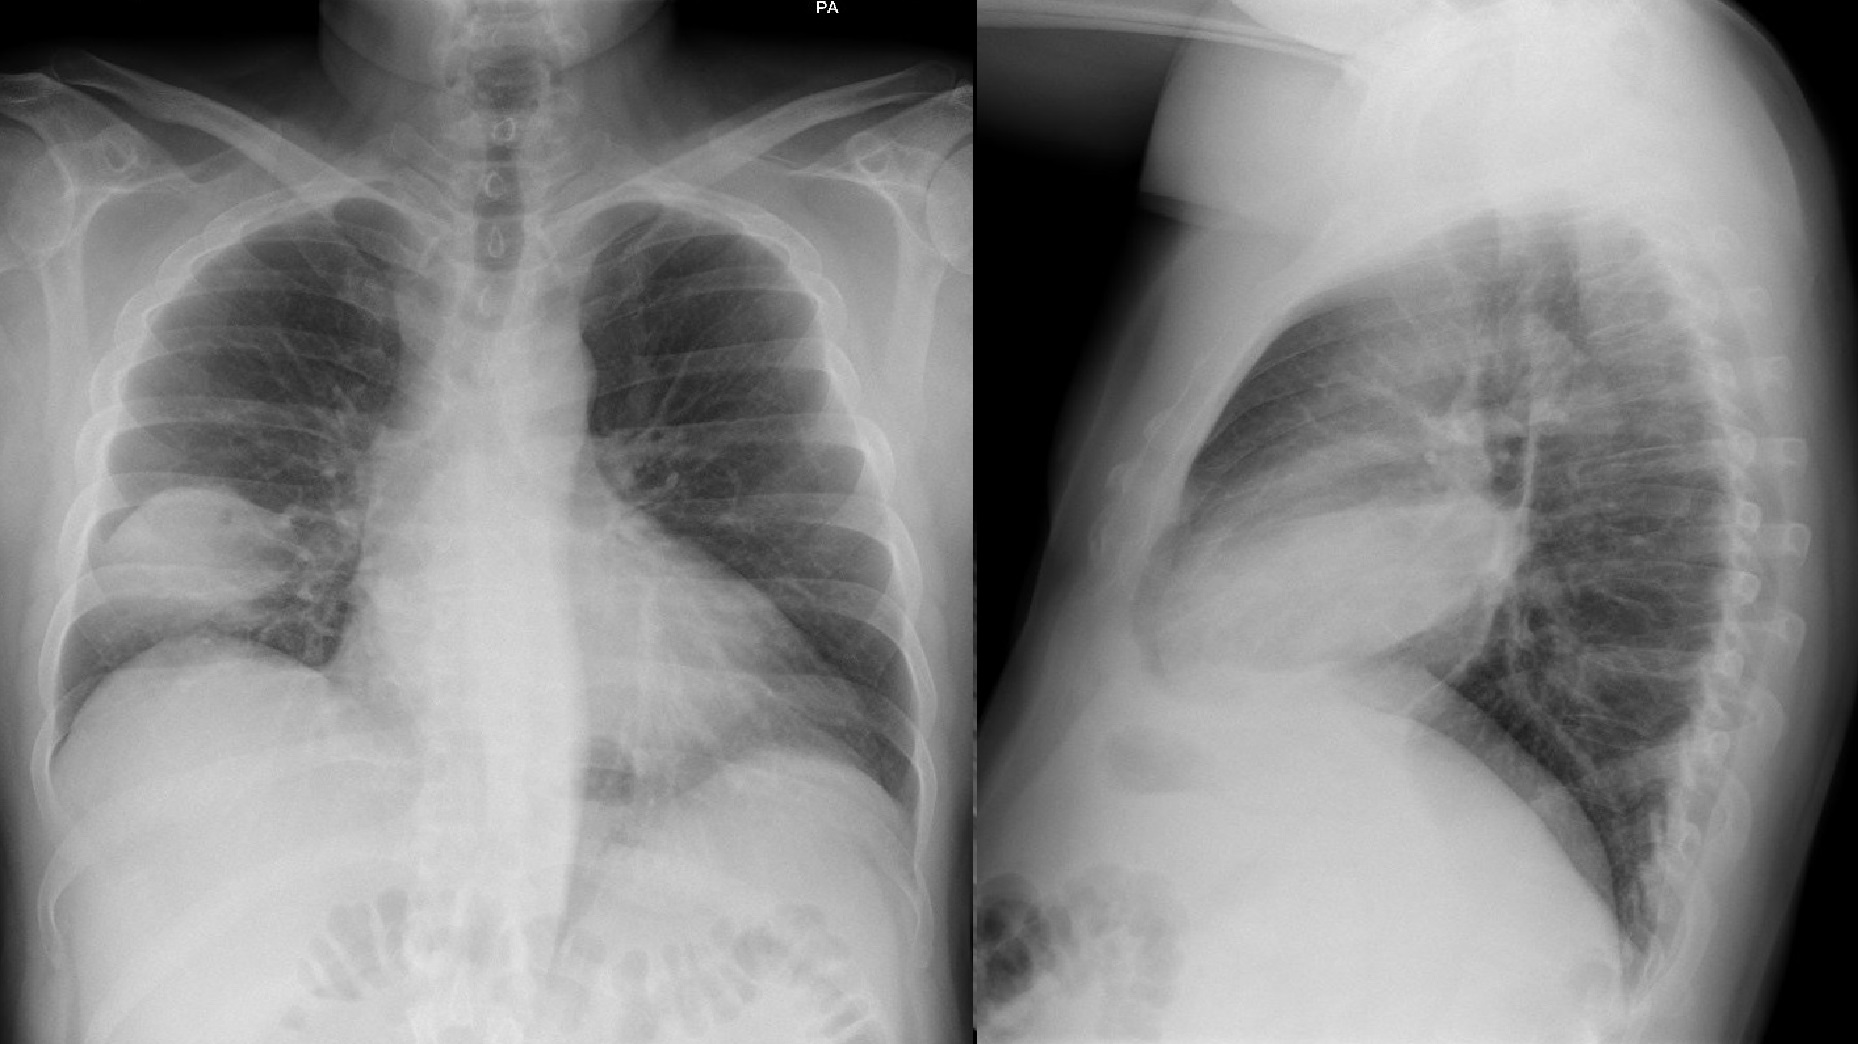

Otras pruebas complementarias realizadas (si existen)

Desaparición de síntomas en los primeros dos días. Seguimiento ecográfico que muestra la desaparición de la neumonía a los 15 días en el primer caso y reducción paulatina del tamaño de la lesión en el segundo.

Se trata de dos casos en los que los hallazgos clínicos y las pruebas complementarias convencionales no hubieran llevado al diagnóstico ni tratamiento adecuados. En el primer caso por una radiografía normal y en el segundo por sintomatología no sospechosa que podría no haber indicado dicha radiografía. La disponibilidad de ecógrafo en la consulta facilita su utilización de inmediato tras la auscultación, detectando las lesiones y consiguiendo una mayor precisión diagnóstica y terapéutica.